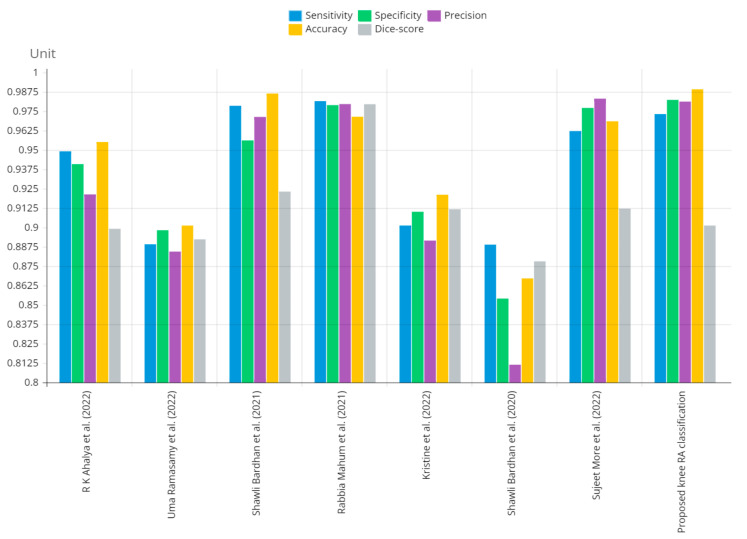

The presented model achieved 99.10% accuracy on the whole test set. The confusion matrix of the presented method is shown in Figure 8, and its performance is compared in detail to that of current methods in Table 5. In Figure 8, we examine the training and learning procedure as a whole to assess the planned activity’s success. Table 6 demonstrates the highest accuracy rate for classifying CBD grades zero–three–four knee joints. The knee joints with a CBD grade of one or two are the toughest to categorize. As can be seen in Figure 8, there is only a marginal amount of room for error when classifying knee joints as CBD Grades zero, three, or four. Knee joints that are classified as CBD Grades one or two have a small number of marginal misclassifications. In several circumstances, the proposed approach incorrectly estimated CBD Grade two as Grade one and vice versa. Joint space narrowing and bony spur development are significantly different in CBD Grade four knee joints. However, CBD-grade one knee joints show little change in JSN or osteophyte growth compared with the other classes. Types of knee RA and their intensity levels are shown in Figure 5. Table 8 and Figure 9 illustrate the JSN accuracy of the proposed and other state-of-the-art methods comparison.

In this study, we developed a deep learning model to automatically grade the severity of knee RA using a consensus-based approach. We compared the proposed work to prior strategies and found that it outperformed the competition. At the elementary level, notably in Grade one and Grade two, we found that our method differed from that of the medical professionals. We evaluated the presented work by comparing its results with similar existing studies. Compared with previously existing models, the presented work (a knee joint space narrowing diagnosis and class label) fares very well. It takes about 7 h of training to reach 0.6 k iterations. The outcomes of the presented methodology are shown in Table 9, which includes the outcomes of each CBD grade individually. Multiple metrics were employed to estimate the model’s performance, as indicated in Table 10. Figure 10 and Figure 11 depict the ROI curve for RA severity classification for both knees.

Table 9: Presented and conventional methods performance metric comparison.

| Techniques/Parameters | Measuring Parameters | ||||

|---|---|---|---|---|---|

| Sensitivity | Specificity | Precision | Accuracy | Dice Score | |

| Shawli Bardhan et al. (2021) [ref. 3] | 0.9785 | 0.9561 | 0.9713 | 0.9864 | 0.9231 |

| R K Ahalya et al. (2022) [ref. 5] | 0.9491 | 0.9408 | 0.9213 | 0.9551 | 0.8991 |

| Sujeet More et al. (2022) [ref. 6] | 0.9622 | 0.9771 | 0.9831 | 0.9685 | 0.9121 |

| Rabbia Mahum et al. (2021) [ref. 9] | 0.9815 | 0.9789 | 0.9896 | 0.9714 | 0.9795 |

| Kristine et al. (2022) [ref. 7] | 0.9012 | 0.9101 | 0.8915 | 0.9211 | 0.9117 |

| Uma Ramasamy et al. (2022) [ref. 31] | 0.8891 | 0.8982 | 0.8844 | 0.9012 | 0.8923 |

| Shawli Bardhan et al. (2019) [ref. 32] | 0.8889 | 0.8541 | 0.8114 | 0.8671 | 0.8781 |

| Presented knee RA classification | 0.9731 | 0.9823 | 0.9812 | 0.9910 | 0.9012 |

Figure 12 shows that the presented system outperformed other methods in terms of sensitivity (Se), specificity (Sp), precision (Pr), accuracy (Acc), and dice score (Ds), demonstrating deep learning’s capability. Figure 13 depicts the CBD grade outcome doughnut chart. In this research, the presented model increased overall ROI detection accuracy by up to 0.5 percent and improved classification accuracy by up to 1.18 percent. The proposed model is more dependable as a result of the detailed knee JSN characteristics. The improvement was satisfactory, and we agree with the observation that the AP view has a significant portion of the information necessary to assess the severity of knee RA with the CBD grading system. The CBD score is often examined using the AP view alone. Table 6 presents a comparison of the output of the proposed methodology with that of other methods that are currently in use. R K Ahalya et al. (2022) obtained Se of 0.9491, Sp of 0.9408 Pr of 0.9213, Acc of 0.9551 and Ds 0.8991; Uma Ramasamy et al. (2022) achieved Se of 0.8891, Sp of 0.8982, Pr of 0.8844, Acc of 0.9012, and Ds of 0.8923; Shawli Bardhan et al. (2021) obtained Se of 0.9785, Sp of 0.9561, Pr of 0.9713, Acc of 0.9864, and Ds of 0.9231; Rabbia Mahum et al. (2021) achieved Se 0.9815, Sp of 0.9789, Pr of 0.9896, Acc of 0.9714, and Ds of 0.9795; Kristine et al. (2022) obtained Se of 0.9012, Sp of 0.9101, Pr of 0.8915, Acc of 0.9211, and Ds of 0.9117; Shawli Bardhan et al. (2020) achieved Se of 0.8889, Sp of 0.8541, Pr of 0.8114, Acc of 0.8671, and Ds of 0.8781; and Sujeet More et al. (2022) obtained Se of 0.9622, Sp of 0.9771, Pr of 0.9831, Acc of 0.9685, and Ds of 0.9121. Our active deep CNN model acquired a knee joint identification accuracy of 98.97% and a knee RA severity classification accuracy of 99.10% using the presented methodology. This model also gives superior performance to handmade features. The active deep CNN model that we have presented and the pre-trained domain adaptation models that are employed in our system produce improved prediction accuracy outcomes for the five classes of knee RA that were experimentally determined.